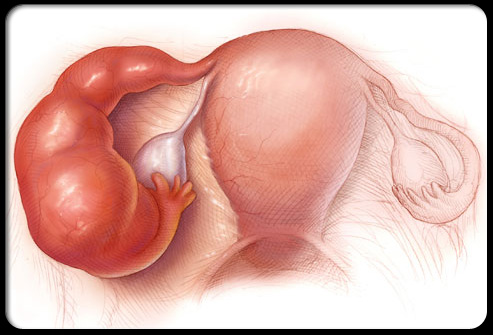

异位妊娠(宫外孕)

宫外孕指胚胎在子宫外着床发育,会导致尖锐的盆腔疼痛,通常出现在身体一侧,并可能伴有阴道出血、恶心和晕眩。宫外孕如果发现得足够早,是可以通过药物治疗的,但是如果出血或输卵管破裂,那么需要紧急手术治疗。